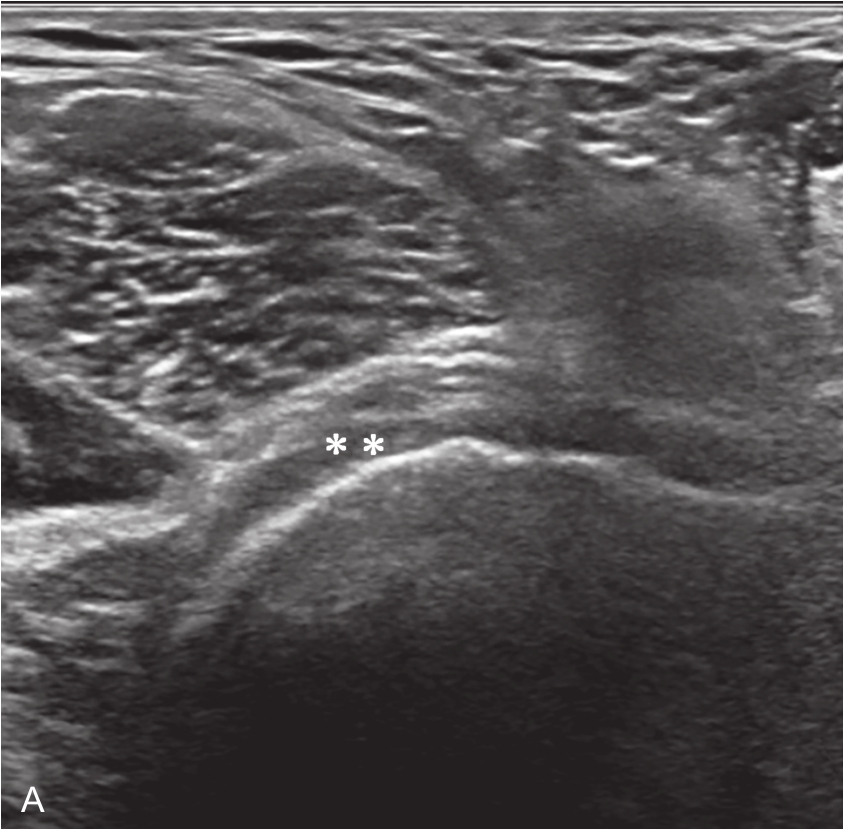

▲ 图2-6-3 超声引导下肩关节腔介入治疗超声图(一)

A、B.二维超声显示肩关节腔少量积液,滑膜增厚;C.超声引导针尖进入关节腔;D.超声示意图,虚线蓝色区域:后关节腔;单星号:腋下关节囊;双星号:后关节腔;短箭头:穿刺针;长箭头:穿刺针路径;L:盂唇;HH:肱骨头